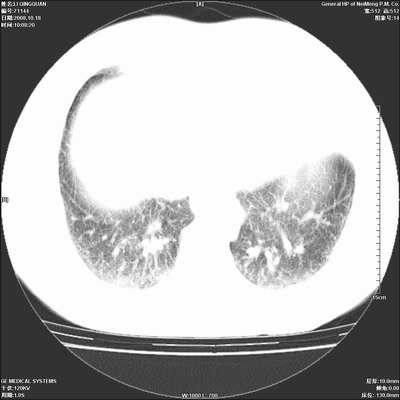

以下是引用duguo在2008-10-19 13:59:00的发言:[br]左肺上叶支气管狭窄,首先考虑中心型肺癌伴阻塞性肺炎\\肺不张.

以下是引用ybing在2008-10-19 12:58:00的发言:[br]左肺上叶阻塞性炎症-建议支气管镜进一步检查除外中央型肺癌

以下是引用随光逐影在2008-10-19 14:31:00的发言:[br]考虑左肺中央型肺癌并左肺上叶阻塞性肺炎,肺不张。